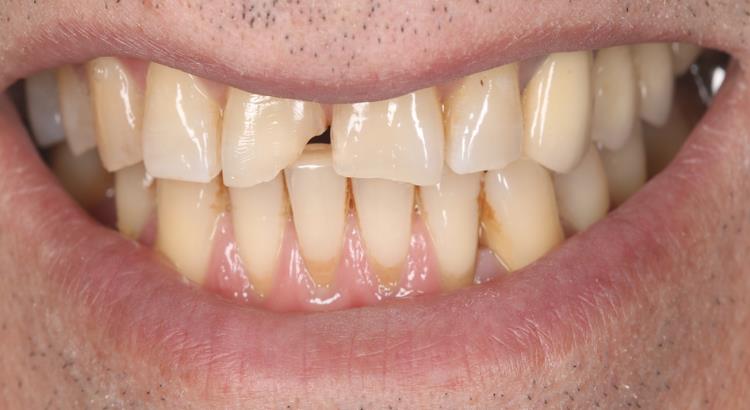

Güvenebileceğiniz Sonuçlar